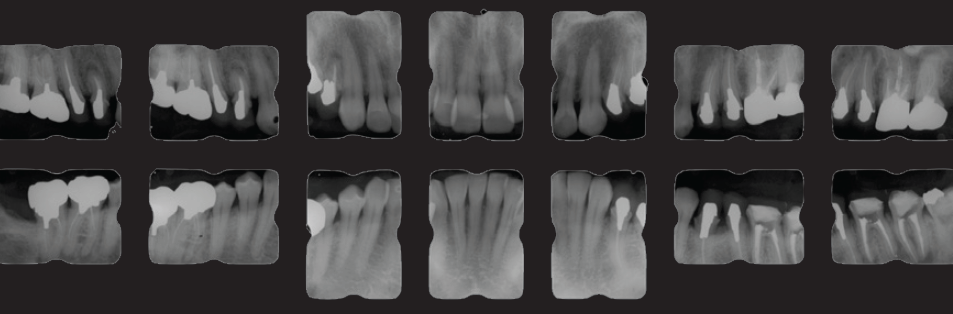

<緊急処置後、初期治療前の口腔内写真と14枚法>

歯周病の程度は軽度。前歯部開口咬合状態を呈し、

既往歴はほぼ臼歯部に集中している

口腔内の傾向から臼歯に過度な負担があり、

さまざまな病態に至っていると推測する

(図19-1)

(図19-2)

<臼歯部の感染根管治療終了後の14枚法>

(図20)

術前には数歯に根尖病変を疑う透過像が確認できたが

術後改善傾向にあることが確認できる